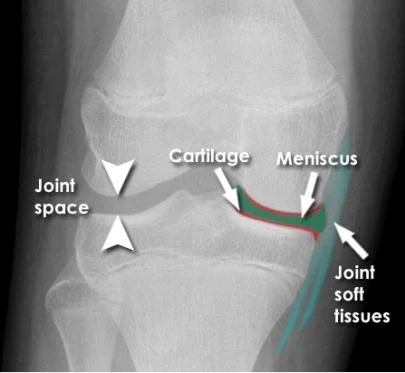

Reading Joints

- Position

- Relations

- Alignment

- Joint âSpaceâ

- Joint line

- Subchondral bone

Joint Position and Relations

Joint Anatomy

- The annotations include:

- Joint space

- Cartilage

- Meniscus

- Joint soft tissues

Bone and Joint Alignment

Joint Space